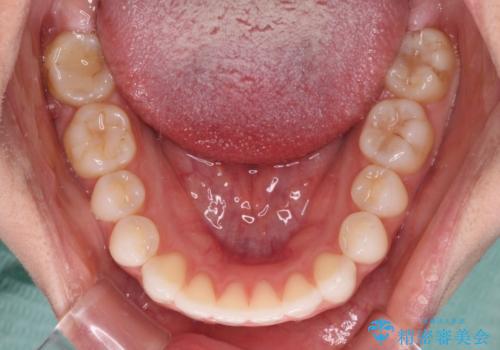

上下前歯が接触しない オープンバイトをインビザラインで改善

- 前歯の上下スペースによる食べにくさを気にして来院された患者様です。

インビザラインにより上下の前歯の隙間を閉じていくこととしました。

上下の奥歯を圧下させるようにすることで、前歯を接触させるように計画しました。

上下の隙間に舌が入り込むことがオープンバイトの原因であったため、舌の筋肉のトレーニングも並行して行い、後戻りの抑制を図りました。